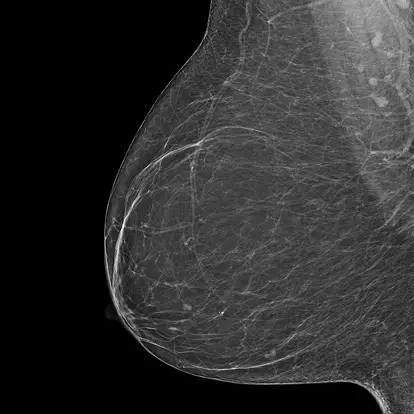

Bi-Rads A

The breast tissue is almost entirely fatty and not dense.